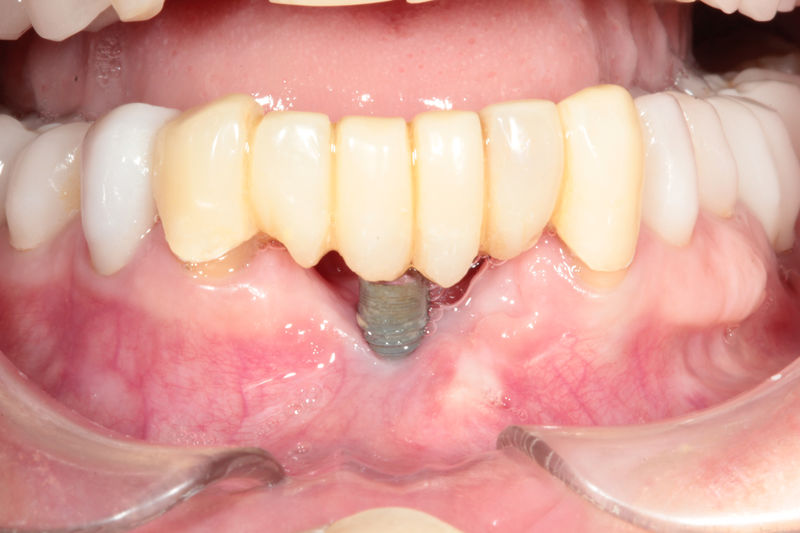

Los implantes dentales son pequeños tornillos de titanio u otro material biocompatible que se insertan en el hueso maxilar o mandibular para sustituir la raíz de un diente perdido. Actuando como un soporte sólido sobre el cual el dentista puede colocar un diente artificial (corona), un puente o una prótesis completa.

Son estructuras de titanio las cuales se colocan en el hueso y se utilizan para soportar coronas, prótesis fijas, removibles y totales. La colocación de los implantes se hacen previo análisis tomográfico.

Implante fracasado, extracción, carillas, coronas y prótesis fija.